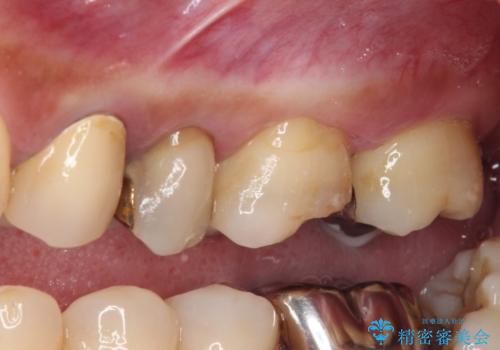

- 奥歯を治療しようと他院で開始したものの、放置してしまったとのことで来院された患者様です。

外れてしまった銀歯や穴の空いた仮歯などあり、適合の悪い被せものと合わせて、セラミッククラウンやセラミックインレーにて治療と行うこととしました。